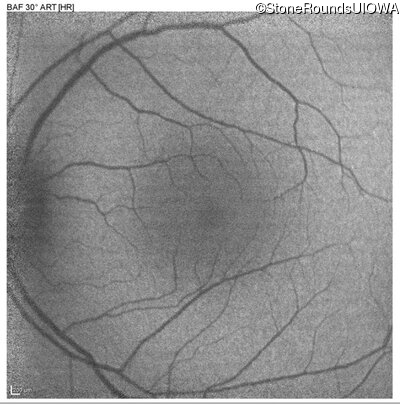

Blue Autofluorescence - Right - 20/25

Exemplar